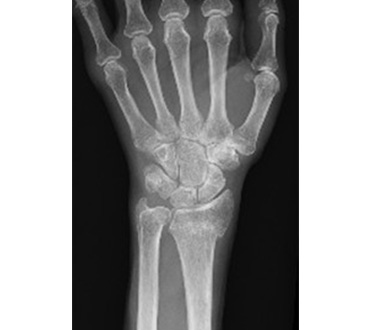

一般撮影室

主にレントゲン写真と呼ばれていてX線を利用し、胸部、腹部、骨などの撮影をします。人体にX線をあて透過したX線をコンピュータで処理し画像にします。迅速に画像を提供できることから、日常の診断に最も多く利用されている検査です。